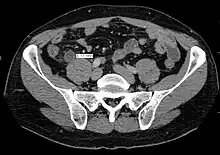

Computed tomography

Where it is readily available, computed tomography (CT) has become frequently used, especially in people whose diagnosis is not obvious on history and physical examination. Although some concerns about interpretation are identified, a 2019 Cochrane review found that the sensitivity and specificity of CT for the diagnosis of acute appendicitis in adults was high.[63] Concerns about radiation tend to limit use of CT in pregnant women and in children, especially with the increasingly widespread usage of MRI.[64][65]

The accurate diagnosis of appendicitis is multi-tiered, with the size of the appendix having the strongest positive predictive value, while indirect features can either increase or decrease sensitivity and specificity. A size of over 6 mm is both 95% sensitive and specific for appendicitis.[66]

However, because the appendix can be filled with fecal material, causing intraluminal distention, this criterion has shown limited utility in more recent meta-analyses.[67] This is as opposed to ultrasound, in which the wall of the appendix can be more easily distinguished from intraluminal feces. In such scenarios, ancillary features such as increased wall enhancement as compared to adjacent bowel and inflammation of the surrounding fat, or fat stranding, can be supportive of the diagnosis. However, their absence does not preclude it. In severe cases with perforation, an adjacent phlegmon or abscess can be seen. Dense fluid layering in the pelvis can also result, related to either pus or enteric spillage. When patients are thin or younger, the relative absence of fat can make the appendix and surrounding fat stranding difficult to see.[67]